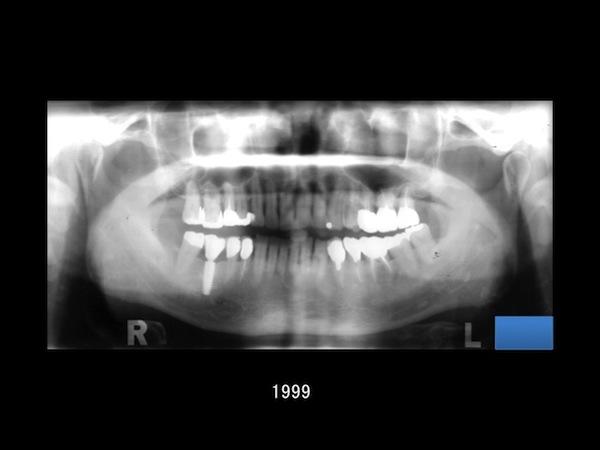

2015.04.01歯科医としての"積み重ね"が生んだ19年の記録 ─ 患者さんとの歩みから学んだこと** -